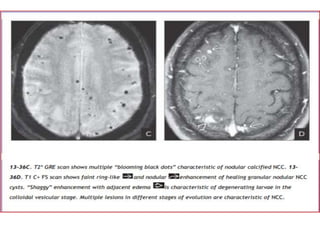

Stages

There are four main stages (also known as Escobar's pathological

stages):

• Vesicular: viable parasite with intact membrane and therefore no

host reaction.

• Colloidal vesicular: parasite dies within 4-5 years untreated, or

earlier with treatment and the cyst fluid becomes turbid. As the

membrane becomes leaky oedema surrounds the cyst. This is the

most symptomatic stage.

• Granular nodular: oedema decreases as the cyst retracts further;

enhancement persists.

• Nodular calcified: end-stage quiescent calcified cyst remnant; no

oedema.

Granular nodular

• Odema decreases

• Cyst retracts

• Enhancement persists but is less marked

• NECT shows mild residual edema. CECT demonstrates an

involuting, mildly to moderately enhancing nodule.

• The cyst wall appears thickened and retracted, and the perilesional

edema diminishes substantially, eventually disappearing. Nodular or

faint ring-like enhancement is typical at this stage

Nodular calcified stage

• End-stage quiescent calcified cyst remnant

• No oedema

• No enhancement on CT

• Signal drop out on T2 and T2* sequences

• Some intrinsic high T1 signal may be present

• Long term enhancement may be evident on

MRI, and may predict ongoing seizures

Stages There are fourmain stages (also known as Escobar's pathological stages): • Vesicular: viable parasite with intact membrane and therefore no host reaction. • Colloidal vesicular: parasite dies within 4-5 years untreated, or earlier with treatment and the cyst fluid becomes turbid. As the membrane becomes leaky oedema surrounds the cyst. This is the most symptomatic stage. • Granular nodular: oedema decreases as the cyst retracts further; enhancement persists. • Nodular calcified: end-stage quiescent calcified cyst remnant; no oedema.

Granular nodular • Odemadecreases • Cyst retracts • Enhancement persists but is less marked • NECT shows mild residual edema. CECT demonstrates an involuting, mildly to moderately enhancing nodule. • The cyst wall appears thickened and retracted, and the perilesional edema diminishes substantially, eventually disappearing. Nodular or faint ring-like enhancement is typical at this stage

Nodular calcified stage •End-stage quiescent calcified cyst remnant • No oedema • No enhancement on CT • Signal drop out on T2 and T2* sequences • Some intrinsic high T1 signal may be present • Long term enhancement may be evident on MRI, and may predict ongoing seizures